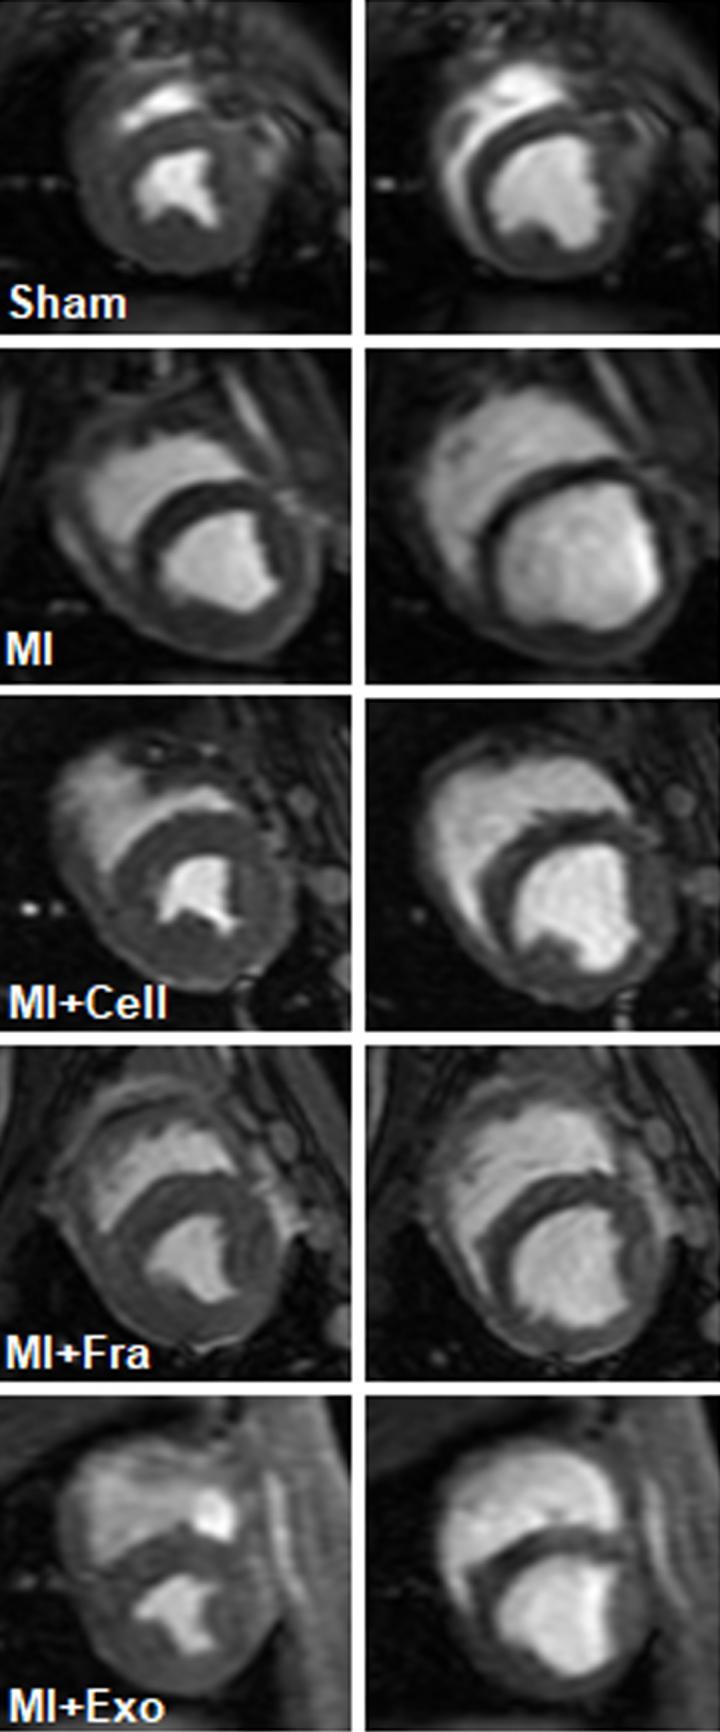

Ling Gao and colleagues have developed a strategy that uses exosomes - tiny membrane-bound sacs secreted by cells - to mimic the heart-regenerating effects of cardiac cell transplants, while potentially avoiding risks associated with whole-cell transplants. Their approach, which accelerated recovery from heart attack in pigs, could address issues with safety and effectiveness that have prevented whole-cell heart therapies from reaching clinical adoption. In recent years, researchers have explored the possibility of using transplants of heart cells grown from induced pluripotent stem cells to heal cardiac tissue in the aftermath of events such as heart attacks. However, transplanted heart cells often fail to engraft within the recipient and perish after a few days. Clinicians also remain worried that the cells that do engraft could cause severe health issues like arrythmia and even contribute to the formation of tumors in the long run. Instead of transplanting whole cells, Gao et al. tackled these issues by only administering exosomes, or tiny containers for proteins and DNA that are secreted by cells. Specifically, they isolated exosomes from three types of human heart cells - smooth muscle cells, cardiomyocytes, and endothelial cells - and injected them into the hearts of pigs after heart attack. Pigs that received the exosomes recovered more heart function and showed smaller scars compared with untreated animals and improved as well as pigs that received whole cell transplants. Gao et al. say that the acellular exosomes "could enable physicians to exploit the cardioprotective and reparative properties of hiPSC-derived cells while avoiding complexities associated with cell storage, transportation, and immune rejection."